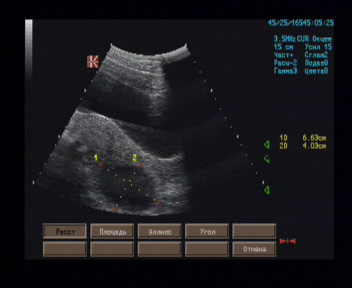

Матка размерами 70 х 67 х 41 мм, anteflexio, грушевидной формы, типичного расположения, контуры ровные, чёткие, миометрий изоэхогенный, однородный, полость щелевидная, эндометрий толщиной 11 мм, в просвете дополнительные эхоструктуры не лоцированы.

К задней стенке перешеечного отдела матки слева прилежит жидкостное гладкостенное образование размерами 65 х 48 х 45 мм, имеющее однородное содержимое.

Правый яичник прикрыт тенью кишечника.

Левый яичник 35 х 19 мм, овальной формы, типичного расположения, контуры ровные, чёткие, корковый слой и центральная зона умеренно дифференцированы, гипоэхогенные, фолликулы не лоцированы.

Регионарные лимфатические узлы не визуализируются.

Эхографические признаки жидкостного образования позади матки слева.